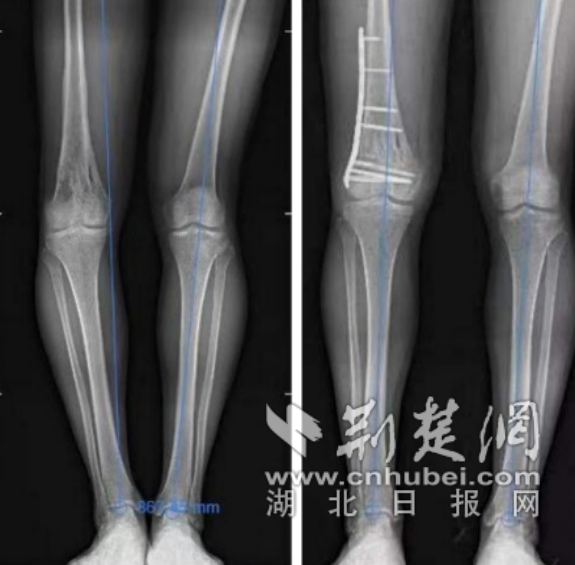

术前、术后正侧位及站立位力线对比 通讯员供图

脊柱外科主任傅兰清接诊后,经详细查体发现,王先生右膝关节僵硬、内翻畸形明显,习惯屈曲活动度只有5°-20°,拍片检查可见重度“右膝关节内翻”,在明确患者病情后立即带领团队全方位研讨,考虑患者较为年轻,应尽力纠正下肢力线,恢复膝关节活动功能,在与患者及其家属沟通后,决定行右股骨远段截骨矫形手术+右膝关节松解及股四头肌松解止点延长术。

入院后,第一时间完善相关检查,次日便安排了手术。术中,傅兰清主任灵活运用高频电刀逐层分离皮下组织及筋膜,细致地进行膝关节松解,使膝关节可屈曲至110°,后经一系列手法矫正后给予克氏针临时固定,矫正膝关节内翻,手术顺利完成。